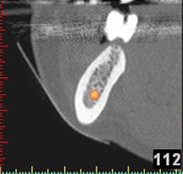

(siehe Bild 3 und 4).

Mit diesen gewonnenen Informationen und Planungen stellt der Zahnarzt interaktiv spezielle Bohrschablonen her. Diese ermöglichen eine exakte Positionierung der Implantate, so wie vorher am Computer geplant.